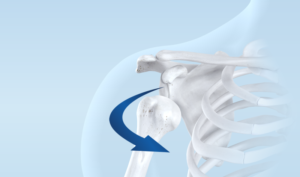

Schultergelenkersatz (Prothese)

Durch die Abnützung des Knorpels kann das Schultergelenk irreversibel geschädigt werden. Aufgrund der Komplexität der Anatomie dieser Körperpartie entwickeln sich unterschiedliche Formen einer Arthrose.

Zu jeder dieser individuellen Ausprägungen gibt es den passenden Prothesentyp (anatomisch, invers, hemi), mit welchem sich nicht nur die Schulterfunktion entscheidend verbessern lässt, sondern auch Schmerzfreiheit angestrebt wird.